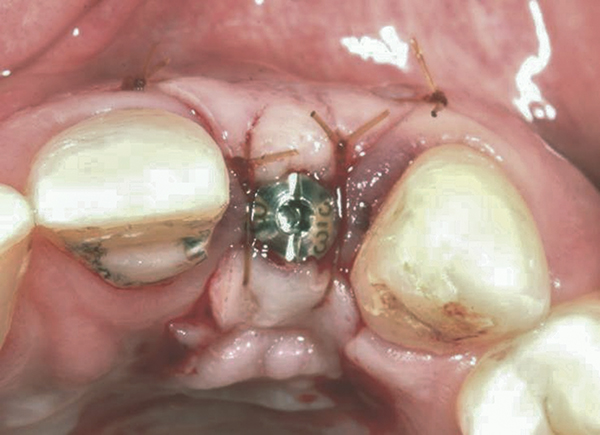

In the esthetic zone it is preferable to avoid elevating papillae because flap elevation may induce recession and create unesthetic black triangles.4 If a flap is necessary to perform a procedure in an edentate area when adjacent teeth are present, the following technique can be used to circumvent blunting papillae. Make a horizontal incision along the midcrestal or palatal aspect of the ridge and terminate the incision 1 mm from the adjacent teeth (Figure 1). The incision is created palatally if it is desired to transpose keratinized tissue to the buccal. From the horizontal incision, create bilateral buccal vertical releasing incisions that extend obliquely at an angle (Figure 2). The vertical incisions can also be extended palatally (for access), but this is not always necessary (Figure 3). Preserved papillae contain gingival supracrestal fibers that subsequently help maintain papillary height (Figure 4). The distance the incision is extended vertically on the buccal is dictated by the task to be accomplished (eg, implant insertion only requires short vertical incisions, while bone grafting needs longer incisions) (Figure 5 and Figure 6). At the end of the surgical procedure, the severed papillary segments are sutured to their retained counterparts (Figure 7 and Figure 8). Figure 1 through Figure 8 demonstrate a submerged implant protocol.

Fig 4. Implant inserted into the ridge, buccal view. There was a large labial concavity. The implant is seen on the buccal and terminates within the alveolar bone.

Figure 4

Fig 14. Implant placed into the thin ridge of bone, occlusal view.

Figure 14

Fig 21. A dental implant was placed at the site of tooth No. 10. A defective buccal ridge was noted.

Fig 22. A straight healing abutment was attached to the implant. The barrier (held back with the periosteal elevator) was placed before the bone graft insertion.

Fig 23. The healing abutment in place. Horizontal and vertical incisions were sutured.